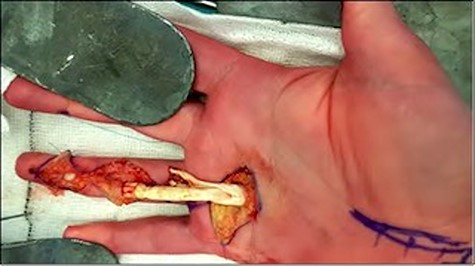

Surgical exploration was performed 4 days later under a general anaesthetic. A Brunner incision was performed at the A5, A3 and A1 levels revealing rupture of both flexor tendons with the proximal limbs held under the A1 pulley (Fig. 1) The tendons were oedematous and the pulleys contracted, so that it was not possible to advance both flexors distally under the A2 pulley. The FDS was therefore resected proximally to the chiasma and the FDP was advanced to the distal phalanx without requiring tendon lengthening. It was inserted using intraosseous fixation to the base of the distal phalanx with 3–0 nylon Bunnell core suture and 5–0 nylon epitendinous sutures to the periosteum of the distal phalanx.